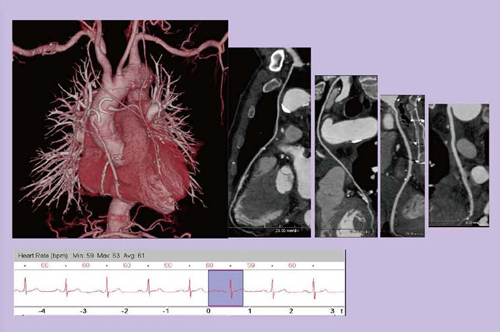

図9は,以前にCABGを施行している胸部大動脈瘤(TAA)の術前症例である。スキャンタイム1.53秒で,広範囲の画像を取得することができ,手術に必要な情報を提供することが可能であった。

図9 65歳,女性,TAA術前